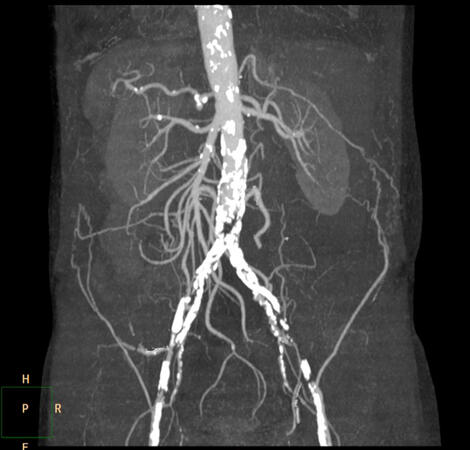

Η νόσος της αορτολαγόνιας περιοχής αναφέρεται στην παρουσία αθηροσκλήρωσης ή άλλων αγγειακών παθήσεων που επηρεάζουν την αορτή και τις λαγόνιες αρτηρίες.

Η αθηροσκλήρωση αφορά την επικάθιση λιπιδίων, χοληστερόλης και άλλων ουσιών στους εσωτερικούς τοίχους των αρτηριών, δημιουργώντας πλάκες. Στο πλαίσιο της νόσου της αορτολαγόνιας περιοχής, αυτές οι πλάκες αναπτύσσονται στην αορτή και τις λαγόνιες αρτηρίες, που αποτελούν σημαντικά αγγεία που μεταφέρουν αίμα από την καρδιά προς το κάτω μέρος του σώματος.

Η νόσος της αορτολαγόνιας περιοχής μπορεί να οδηγήσει σε στένωση ή φραγή των αρτηριών, μείωση της ροής του αίματος προς το λεκάνη και τα πόδια. Αυτή η κατάσταση μπορεί να οδηγήσει σε συμπτώματα όπως διαλείπουσα χολώτητα (πόνος ή κράμπες κατά τη διάρκεια φυσικής δραστηριότητας), αναψυχή ή αδυναμία στα πόδια.

Οι διαγνωστικές μεθόδοι για τη νόσο της αορτολαγόνιας περιοχής περιλαμβάνουν εικονολογικές εξετάσεις όπως αγγειογραφία, υπερήχος ή μαγνητική αγγειογραφία. Οι επιλογές θεραπείας μπορεί να περιλαμβάνουν αλλαγές στον τρόπο ζωής, φαρμακευτική αγωγή και, σε πιο σοβαρές περιπτώσεις, χειρουργικές επεμβάσεις όπως η αγγειοπλαστική ή η χειρουργική επέμβαση για την αποκατάσταση της κανονικής ροής του αίματος.